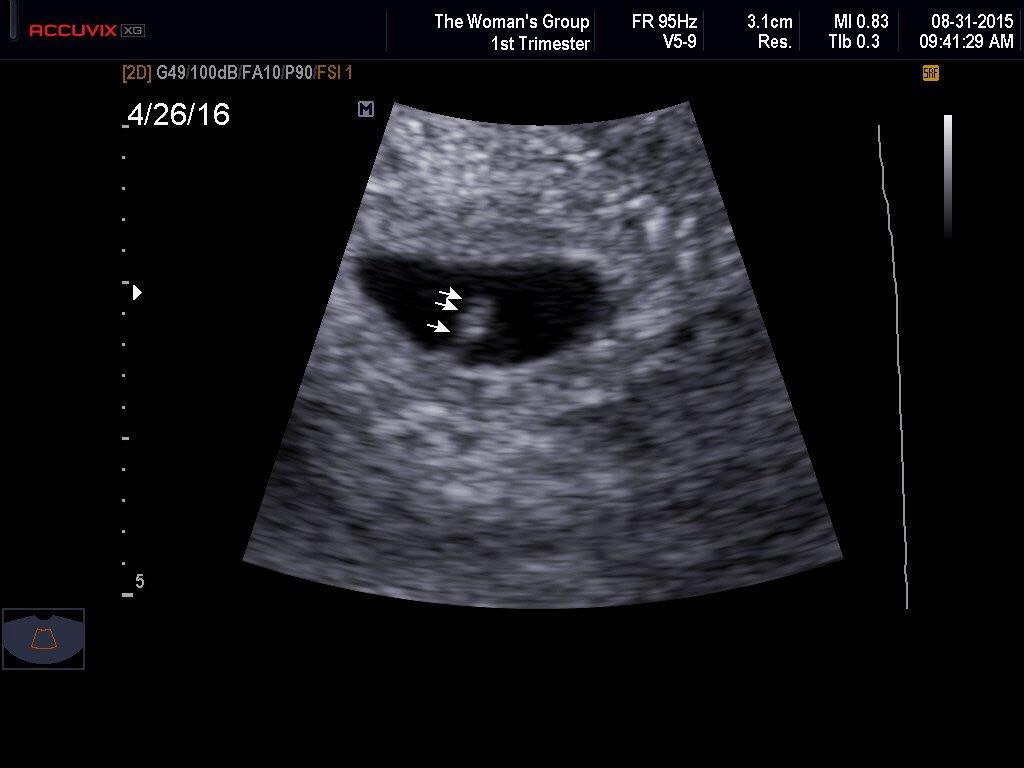

• I can finally join the club! We were finally able to see and hear our little one today. We're measuring 10w, like we thought. Super relieved that all is well!